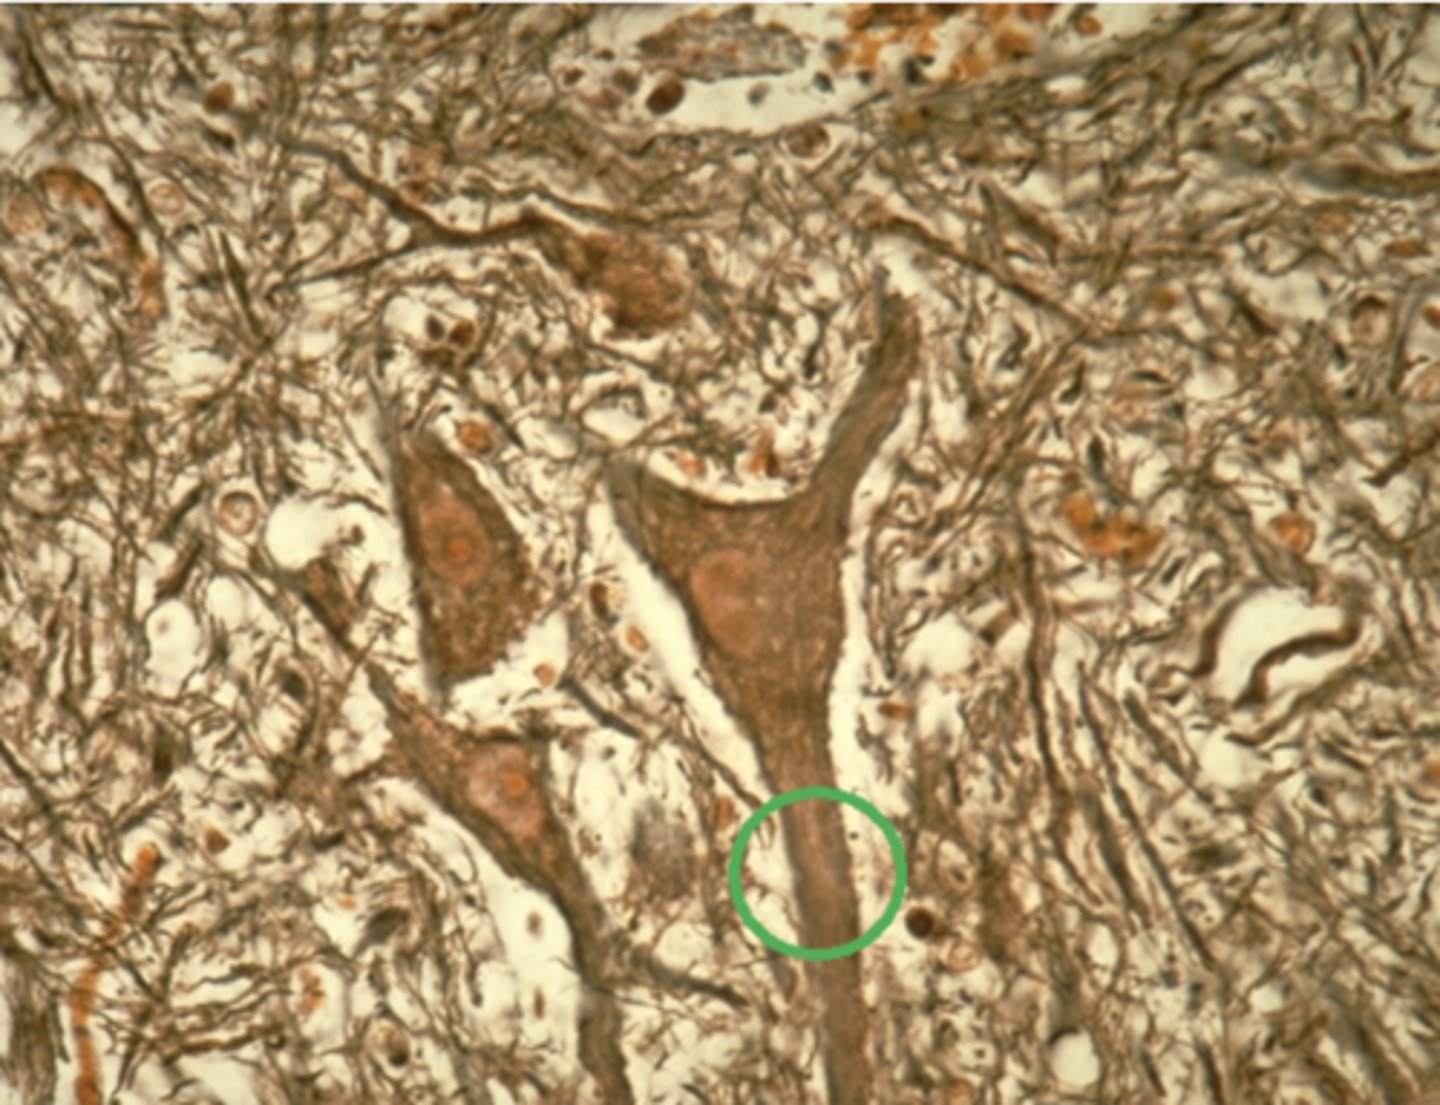

nervous tissue

Which of the four major tissue types is presented in the following image of the spinal cord:

Axon

Which feature, circled in green in the previous image, is responsible for transmitting impulses away from the cell body? Nervous tissue

Cell body

Dendrite

Glial cell

Axon